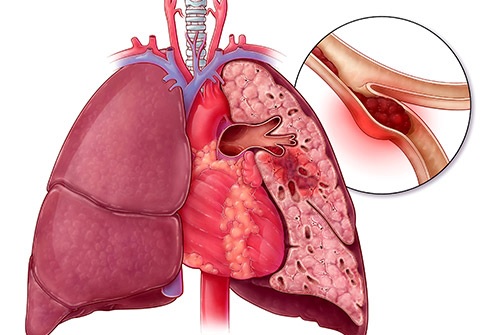

Pulmonary Embolism

This is when a blood clot gets stuck in a blood vessel in one of your lungs. Your chances of having one go up after age 50, and it can be serious, so get medical help fast if you have chest pain, sudden shortness of breath, and dizziness. You also can have a bloody cough, leg pains, and clammy or bluish skin. The blood clot often starts in your leg, so an early sign might be swelling or pain in one of your calves.

Your risk goes up if you’ve had heart disease or recent surgery, or you were in a cramped position (like in an airplane or car) for a long stretch of time.